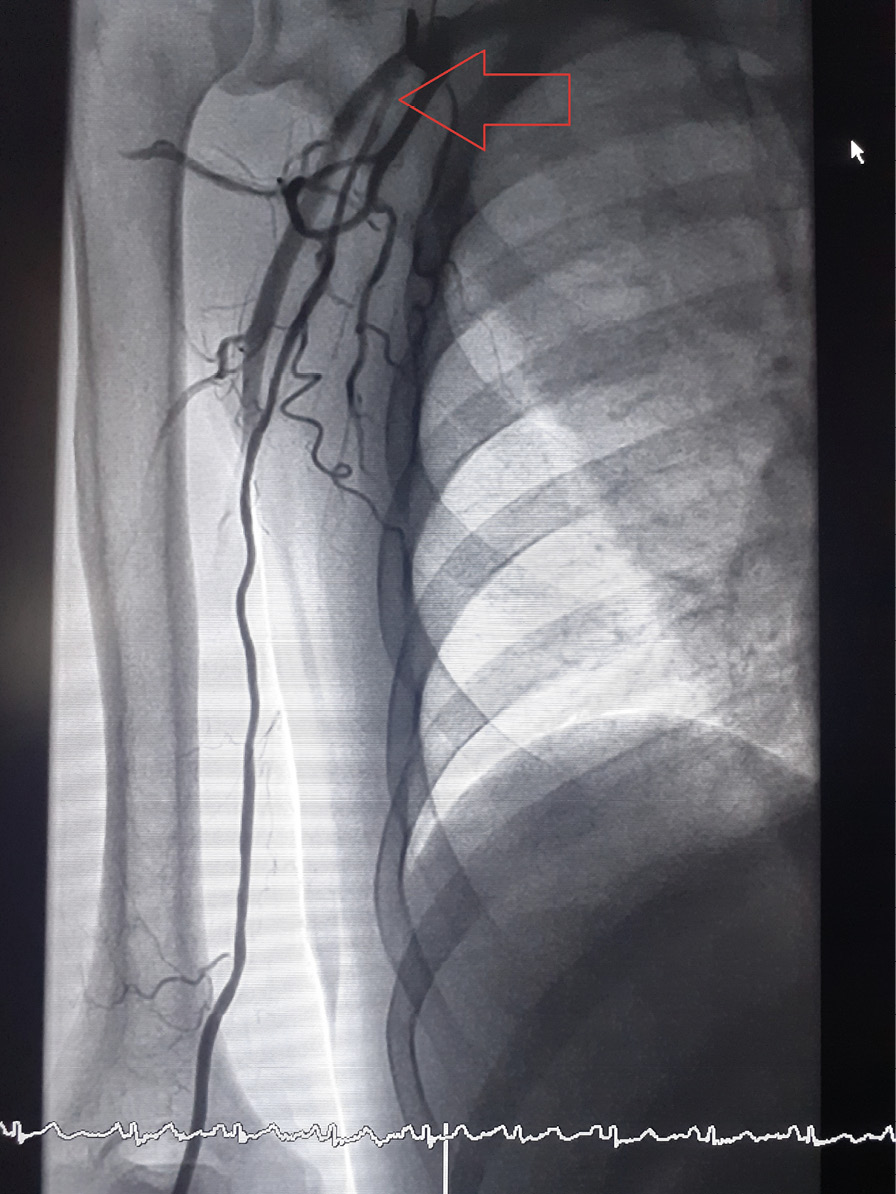

Рис. 2. Дорсопальмарный (модифицированный дистальный) лучевой доступ: контрольная ангиография доступа (красной стрелкой указана область пункции лучевой артерии, зеленой стрелкой – поверхностная ладонная ветвь лучевой артерии r. superficialis)

Рис. 3. Аберрантная лучевая артерия, отходящая от подмышечной артерии (уровень отхождения указан красной стрелкой)